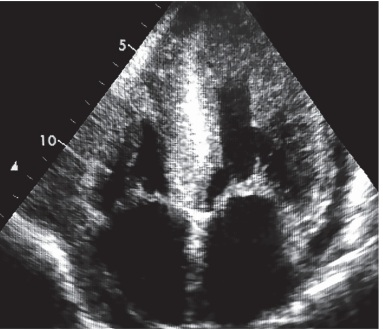

Mulher de 79 anos é encaminhada para realização de ecocardiograma transtorácico com vistas a

esclarecimento de padrão de cardiomiopatia dilatada (ICFEr) associada a proteinúria nefrótica e discretas

equimoses peripalpebrais. O exame complementar revela um brilho intenso no septo interventricular

(fi gura abaixo) associado ao padrão “apical sparing”.